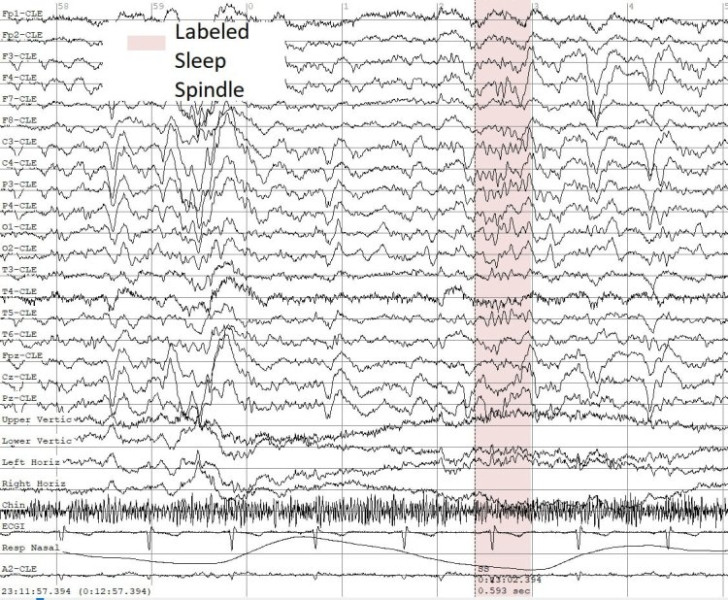

Пример паттернов сна (сонных веретен) в записях ЭЭГ. Иллюстрация предоставлена пресс-службой ННГУ

Один из ключевых этапов разработки был посвящён анализу нейросигналов второй фазы сна. Ритмы мозга, фиксируемые в этом состоянии у здоровых людей, называются «сонные веретёна». Они служат биомаркерами важнейших когнитивных процессов, таких как формирование долгосрочной памяти и усвоение новой информации. При эпилепсии характеристики сонных веретён (плотность, частота, длительность) могут нарушаться, и их автоматический анализ может служить важным биомаркером течения болезни при уже установленном диагнозе. Метод нижегородских учёных позволяет описать и проанализировать эти изменения.